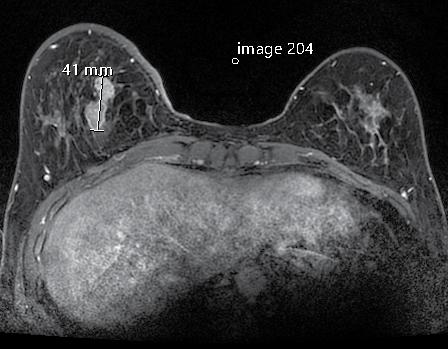

■ Nola Hylton was elected to the National Academy of Medicine, one of the highest honors in medicine, for her pioneering work in breast MRI technology

A Breast Imaging Center of Excellence

“As breast imagers, we’re passionate about early cancer detection and caring for patients, educating our trainees, and being mindful of translational research to improve the standard of care,” said Joe. She highlighted that the center, accredited by the American College of Radiology in Mammography, Breast Ultrasound, Stereotactic Biopsy, and Breast MR, was the first in San Francisco to deploy top-of-the-line digital mammography units, along with dedicated breast ultrasound machines for targeted breast ultrasounds and ultrasound guided biopsies.

“Just as it was the first site to get digital mammography capabilities, I’m proud to tell you it was also the first to get Digital Breast Tomosynthesis,” said Joe, who highlighted what’s next for the future of imaging services at the center.

Digital Breast Tomosynthesis (DBT)

DBT creates a 3D breast image allowing radiologists to examine breast tissue layer by layer. This advanced imaging technique improves cancer detection through better visualization, especially for women with dense breast tissue. DBT is increasingly used for breast cancer screening and diagnostic procedures because it allows easier differentiation of benign and malignant lesions.